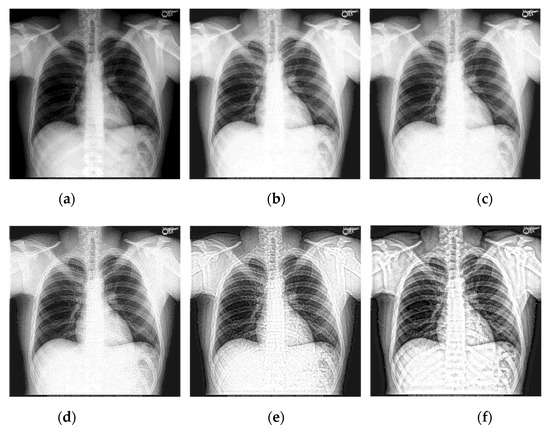

Select two representative medical images for analysis: Image 1 with the size of 440 × 440 and image 2 with the size of 1024 × 1024 . The enhanced X-ray images obtained under different decomposition levels are shown in Figure 3 and Figure 4 where (a) is the original image, and (b–f) corresponds to the decomposition levels j equal to 1–5. When the number of scale decomposition levels is j , NSST decomposition requires 2 j times of image and filter convolution; the running time of the algorithm gradually increases. Observing the image, the image contrast has been significantly improved after histogram equalization. When the decomposition scale j 3 , with the increase of the NSST decomposition scale, the boundary and texture features of the image are gradually obvious, and the detailed information is enhanced. When 5 j > 3 , the enhancement effect is further improved; the change is not significant.

Figure 3. The enhanced effects of different decomposition levels on the X-ray image 1. (a) is the original image, and (bf) corresponds to the decomposition levels j equal to 1–5.